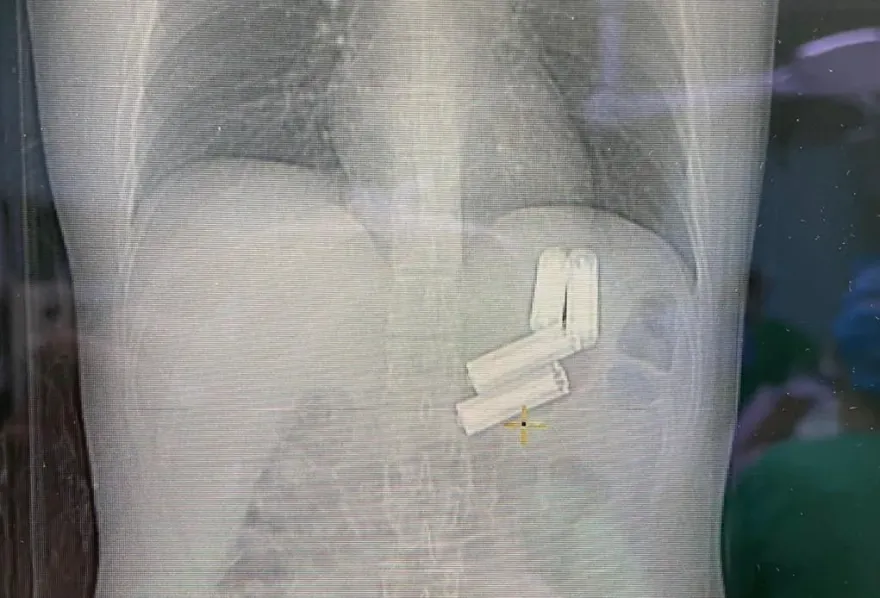

大陸

手術

腹痛

體溫計

吞下

醫院

十二指腸

病患